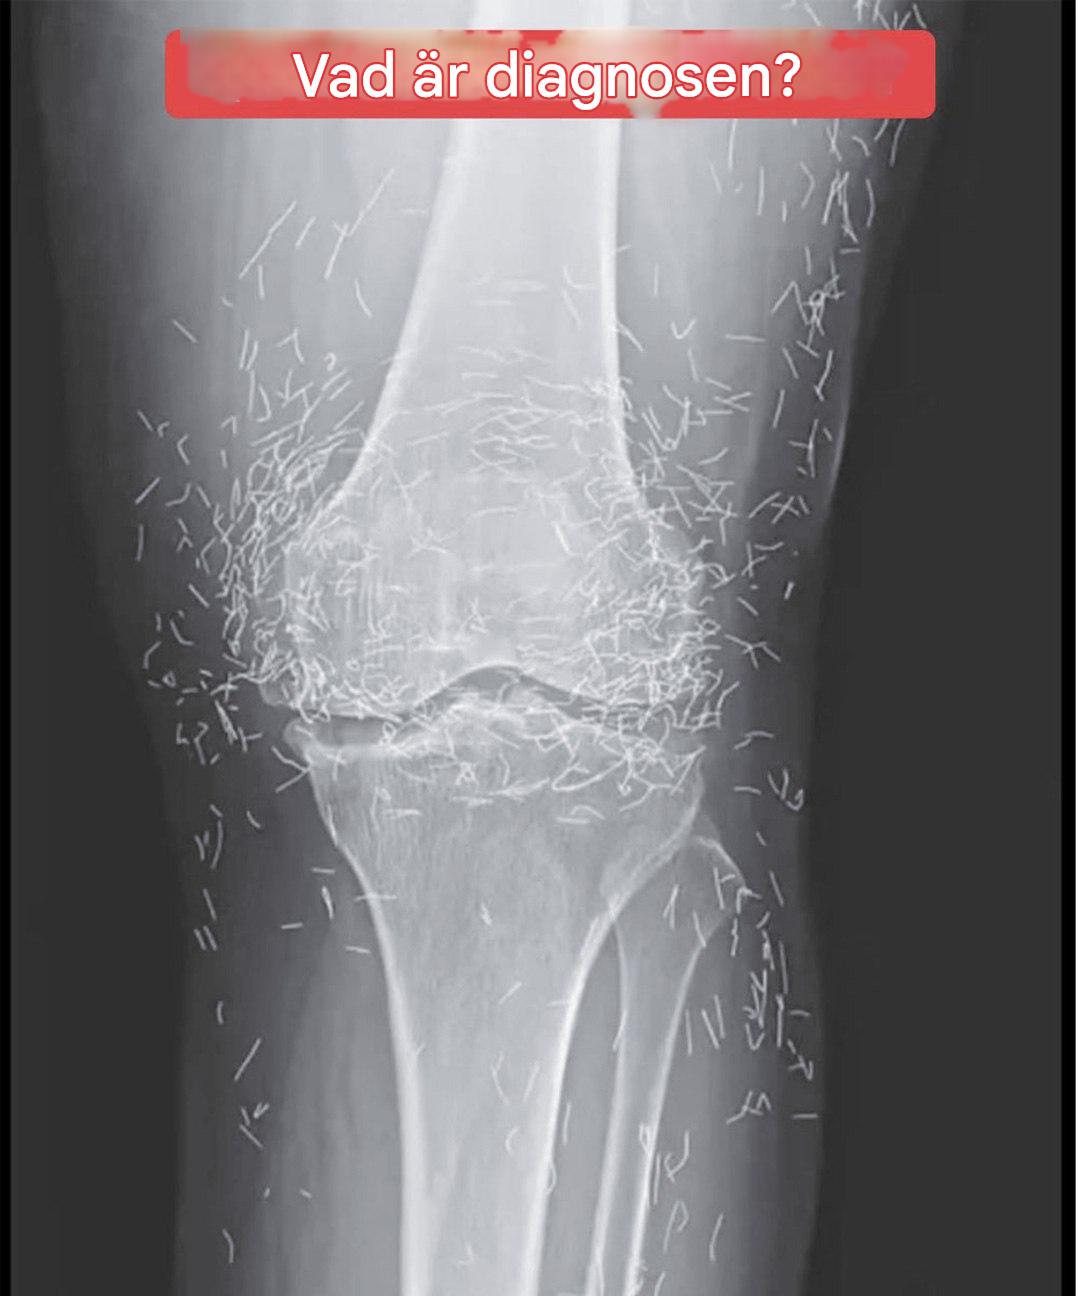

Tänk dig att få en enkel röntgenundersökning av knäsmärta... och upptäcka att din kropp innehåller en riktig gömd skatt! Det var vad som hände en 65-årig kvinna, vars medicinska bilder avslöjade en ganska oväntad närvaro. Det läkarna såg väckte betydligt fler frågor än det besvarade. Och bakom denna spännande bild döljer sig en metod som fortfarande är relativt okänd i Frankrike, men som ändå används flitigt över hela världen...

Vid det här laget vände hon sig till ett välkänt alternativ i Asien: akupunktur. Men inte vilken akupunktur som helst...